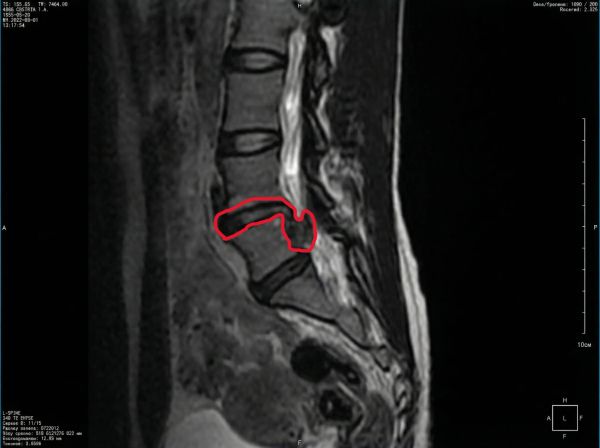

Пациентка, 40 лет. Грыжа позвоночника, 2 сантиметра.

Грыжи нет, остался только рубец.